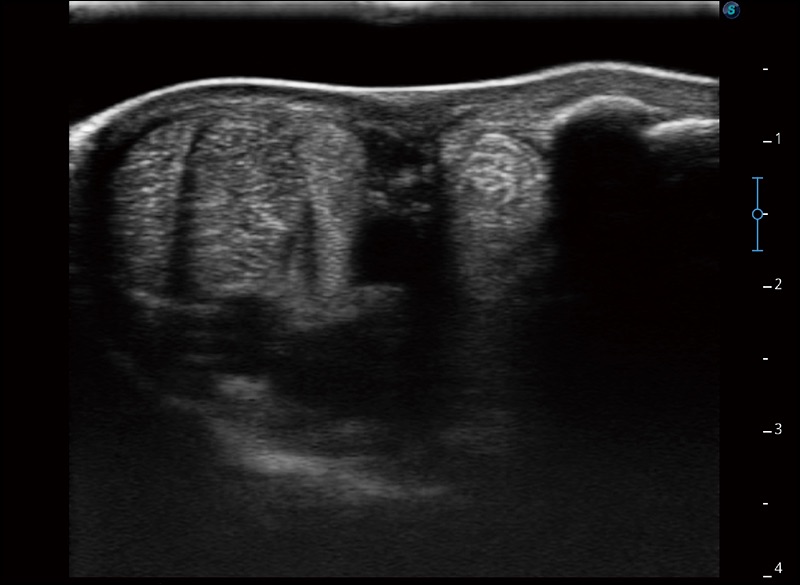

α1卓越的图像质量和便捷的工作流程,使每位宠物医生都能轻松扫查。其全面的兽用应用功能和紧凑型的结构设计,可以满足动物检查的多种需要。专业的预设检查模式和多领域测量软件包有助于为不同类型的动物提供检查, 让宠物医生能够出色的完成工作。